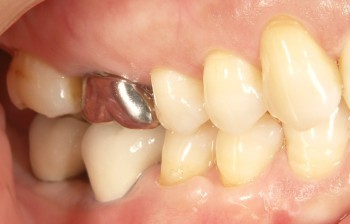

インプラントの術前・術後 Nさん